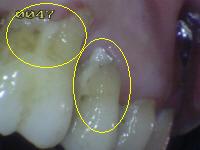

Debe eliminar la placa bacteriana de las superficies (UCE) unión cemento-esmalte por medio del cepillado mecánico o cepillo dental, para poder observar áreas de desmineralización si las hubiere. Ver círculos en amarillo.